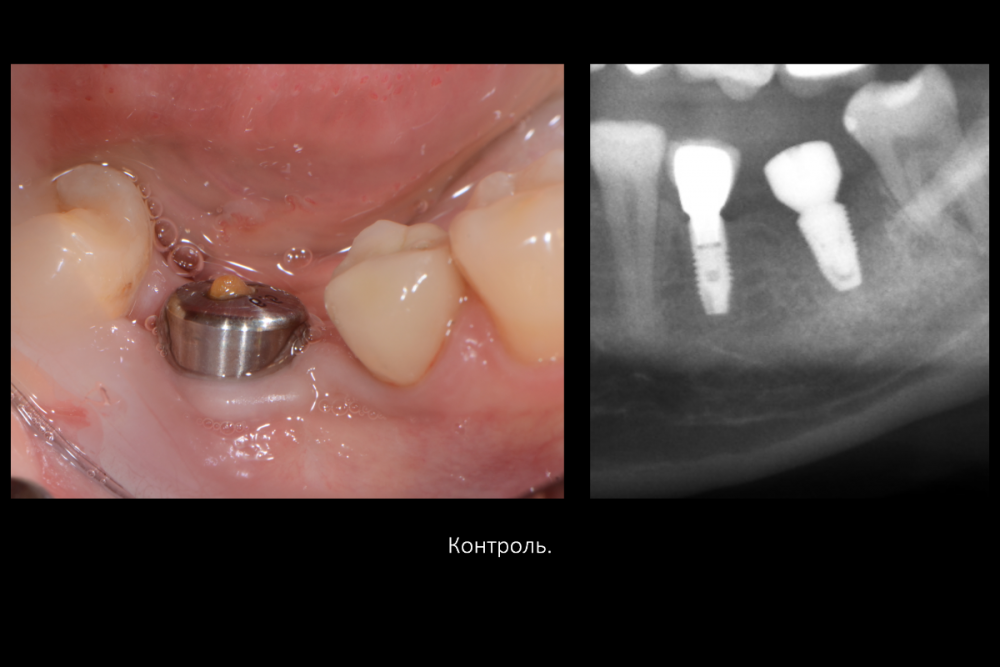

Карен Аванесов Опубликовано 16 июля, 2021 Поделиться Опубликовано 16 июля, 2021 Вариант герметизации послеоперационной раны, когда, хочется установить имплантат и сократить для пациента сроки реабилитации. Итак, "Астра" отличные имплантаты при хороших условиях работают, при экстремальных ситуациях выбор калибров сильно страдает и суживает возможности оператора (очевидно менеджерам не интересно будущее системы, эксклюзивная цацка профайл и маркетинговое продвижение на "озоне" это не то), как по мне, раздутый, абсолютно не удобный хирургический набор, не разделяю восторгов относительно эксклюзивности и предписуемым волшебным свойства, кость наросла! это только на "астре" так или только на анкилозе! На любой системе можно получать результаты. Представляю клинические случаи с одинаковыми условиями, но разными системами, там где "астра" не захотела первичной стабильности, в виду недостаточно широкой талии, "дентиум" диаметром 6мм встал бы на ура, но "астра" такой заказ ортопеда. 8 1 1 3 Ссылка на комментарий

Карен Аванесов Опубликовано 21 февраля, 2022 Автор Поделиться Опубликовано 21 февраля, 2022 Дозрела костна ткань. Возвращаясь к вопросу о "волшебстве" брендовых систем.... Безусловно, молодому специалисту, через сопливый нос бубнить на консультации что от СТАВИТ страуманн, мобель или аштру, поднимает самомнение, окрыляет, иногда и до звездной болезни, помогает быстрее "заматереть,"но сути не меняет. Кость "подрастает" не только аштре например, что иногда демонстрируют с восторгом, но и на отстойном дентиуме тоже, и думаю и на отстойной альфа-био и т.д., т.е. все-же от условий зависит, пациента и конечно техника, что там как и дальше будет. Соберу кейс покажу вошебный рост на голых витках корейского народного ширпотреба)))) 1 Ссылка на комментарий